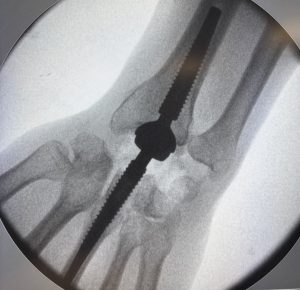

Prothèse totale de poignet à Annecy : traitement de l’arthrose du poignet Chirurgie du poignet à Annecy : quand la